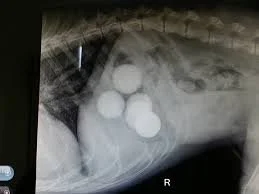

gi foreign body dog

• abdominal radiographs (X-rays)

Radiographs often help identify the presence and location of the obstruction.